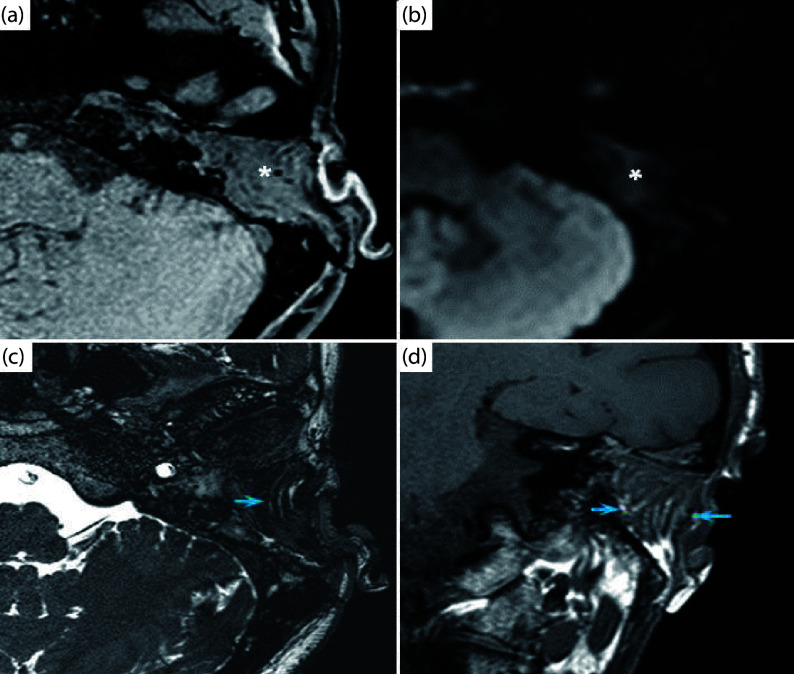

颞骨放射性骨坏死(ORN-TB)通常采用保守措施加以控制。然而,在无反应的病例中,可能需要颞骨切除术。由于辐射对局部组织的损伤,导致缺损的重建可能具有挑战性。因此,远距离自由襟翼可能是最佳选择。例如,股薄肌自由皮瓣(GMFF)具有一致的血管解剖结构,可用于重建小缺陷。我们报告三例不受控制的ORN-TB需要广泛的颞骨切除术,然后用GMFF血管闭塞。患者报告完全控制了主要的耳科症状(耳漏、耳痛和耳充盈),并获得了最佳的功能和美学结果。最后,尽管术后早期出现并发症,患者的生活质量仍有显著改善。据我们所知,GMFF尚未用于消除ORN-TB患者的颞骨缺损。

Osteoradionecrosis of the temporal bone (ORN-TB) is usually controlled with conservative measures. However, a temporal bone resection may be required in unresponsive cases. The reconstruction of the resulting defects may be challenging because of the radiation damage to regional tissues. As a result, distant free flaps may be an optimal choice. For instance, the gracilis muscular free flap (GMFF) has consistent vascular anatomy and can be used to reconstruct small defects. We report three cases of uncontrolled ORN-TB requiring an extensive temporal bone resection followed by vascularized obliteration with a GMFF. The patients reported complete control of the main otologic symptoms (otorrhea, otalgia, and aural fullness) and optimal functional and aesthetic outcomes. Finally, the patients reported significant improvement in quality of life despite early postoperative complications. To our knowledge, the GMFF had not been used to obliterate temporal bone defects in patients with ORN-TB.